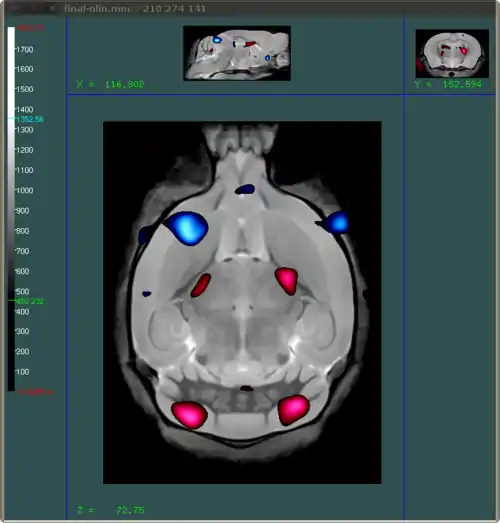

What we want to do is create an image that shows which areas of the brain have a certain t-statistic related to them. Ideally we want to show areas that have negative t-stats and positive t-stats using different colours. The end result should look something like this:

You can load multiple files into Display. In the example above the red shows areas where the t-statistics are at least 4 (and thus positive), and the blue areas indicate areas where the t-statistics are at most -4. All this information comes from one file: the tstats.mnc file. In order to create two different colours using that one file, you will have to load it in twice in Display. That is the first step